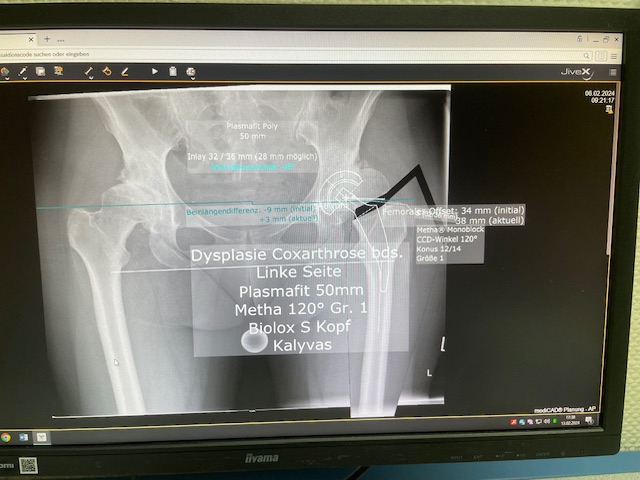

Ο προεγχειρητικός ψηφιακός σχεδιασμός

Ο προεγχειρητικός ψηφιακός σχεδιασμός ήταν ιδιαίτερα μεθοδικός και συγκεκριμένος. Η ακτινογραφία λεκάνης της ασθενούς εισήχθη σε ειδικό λογισμικό στον υπολογιστή, το οποίο επέτρεψε τον ακριβή προγραμματισμό της καινούριας θέσης της άρθρωσης.

Μέσω του ψηφιακού αυτού σχεδιασμού, υπολογίστηκε με ακρίβεια το μέγεθος και ο τύπος των προθέσεων, η γωνία του κώνου, καθώς και η σωστή ανατομική τοποθέτηση των μοσχευμάτων. ώστε να επιτευχθεί τέλειος ισοσκελισμός των κάτω άκρων και να αποφευχθεί οποιαδήποτε διαφορά μήκους μετεγχειρητικά!!!

Πρόκειται για ένα εξαιρετικά σημαντικό στάδιο, καθώς εξασφαλίζει τη μέγιστη δυνατή ακρίβεια, ταχύτητα και αποτελεσματικότητα κατά τη διάρκεια της επέμβασης. Επιπλέον, συμβάλλει στην άριστη λειτουργικότητα του ισχίου καθώς και να επιτευχθεί τέλειος ισοσκελισμός των κάτω άκρων και να αποφευχθεί οποιαδήποτε διαφορά μήκους μετεγχειρητικά!!!

Ο προεγχειρητικός ψηφιακός σχεδιασμός αποτελεί πάντα πλήρως εξατομικευμένο πλάνο, προσαρμοσμένο στα ανατομικά χαρακτηριστικά και τις ανάγκες του κάθε ασθενούς, και είναι καθοριστικός για την επιτυχία της επέμβασης !!!